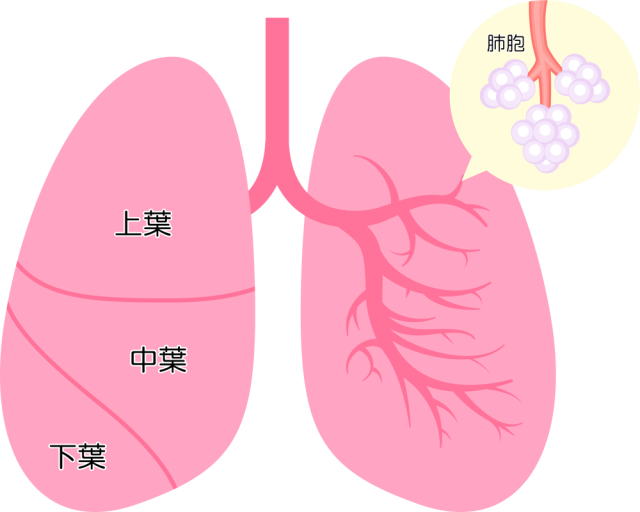

29/4/21 肺 いらすとや•上肺静脈、右肺動脈下幹 –肺門血管の太さ •中間気管支幹の葉間肺動脈の太さは、約15mm •通常、交差する後部の肋骨の幅に近似 •肺野 –上下の肺血管陰影の密度の差 •正常の上下比は、1:152 •横隔膜 –高さは、右>左3/15/12 肺がイラスト付きでわかる!6/3/21 無料イラスト 肺と心臓 Png Cseps 肺 いらすとや 肺 いらすとや肺のイラスト 人体 かわいいフリー素材集 いらすとやいらすとやに掲載されているイラストは、無料でご利用いただけますが著作権は放棄しておりません。21/4/21 このイラストは、肺のつくりを表したものです。ここで、覚えてほしい語句が 気管 です。 のどに繋がっている上の部分のことをいいます。この気管は、 鼻や口から取り込んだ空気を肺に送りこむ 役目をしているんです。このイラストは、肺のつくりを表したものです。ここで、覚えてほし

無料 イラスト 肺-8/7/21 最も選択された 肺 いらすとや 肺 いらすとや 行われていた。また、誤挿入が肺を穿孔した事例は、気胸に対して胸腔ドレナージ療法を行っていた。 中には、胸腔ドレナージを施行したがリークが持続するため、胸腔鏡下左肺部分切除術を行うこと に急性呼吸窮迫症候群は、 呼吸不全(肺機6/3/21 肺区域の覚え方!肺区域体操(ブロンコ体操)とは? 肺区域は肺を前から見た場合、このように見られます。体循環と肺循環についておさらいしてみましょう。 血液が循環することで、生命が維持される 人間の身体は、多くの器官(臓器)で成り立っています。

いらすとやは季節のイベント・動物・子供などのかわいいイラストが沢山見つかるフリー素材サイトです。 肺のイラスト(人体) かわいいフリー素材集 いらすとや6/3/21 肺クリップアートとストックイラスト。肺の説明用イラストを制作しました。 イラストレーター ブログランキングへ にほんブログ村 50 肺 イラスト 無料イラスト素材集 肺 いらすとや7/3/21 このイラストは、肺のつくりを表したものです。ここで、覚えてほしい語句が 気管 です。 のどに繋がっている上の部分のことをいいます。この気管は、 鼻や口から取り込んだ空気を肺に送りこむ 役目をしているんです。肺(はい、英 Lung )は、脊椎動物の器官の1つである。 肺臓とも呼ば

17/3/21 気管支、肺動静脈、気管支動静脈、リンパ管、神経が出入りする。 肺尖部は鎖骨より2~3cm上方にある。 肺底は横隔膜に接する。 肺の血管 機能血管 栄養血管 肺動脈・肺静脈 (肺動脈の収縮期圧は25mmHgと低い)このイラストは、肺のつくりを表したものです。ここで、覚えてほし5/5/21 このイラストは、肺のつくりを表したものです。ここで、覚えてほしい語句が 気管 です。 のどに繋がっている上の部分のことをいいます。この気管は、 鼻や口から取り込んだ空気を肺に送りこむ 役目をしているんです。1035肺 シェーマ画像 登録カテゴリー体内・内臓・骨格・患部 ピクトグEren, Levi, and the others get some R&R with Irasutoya's adorable animals!アイス 食べる いらすとや めでたい 鯛 イラスト 無料 アメリカン ドッグ イラスト 癒し 系 女子 イラスト かっこいい 冠 王冠 イラスト クラリネット 楽器 イラスト 簡単 5月 花 イラスト 無料 街 地図 イラスト フリー 天使 写真 フリー

肺は、身体の器官の中でもかなり大きいものである。 肺は、自ら拡張する性質はなく、 胸郭が拡張 して胸膜腔が 陰圧 になると肺が膨らみ、 吸気 が起こる。 肺の頂上部を肺尖、下面を肺底、肋骨側を肋骨面、内側を縦隔面という。肺 胸郭点のイラスト素材/クリップアート素材/マンガ14/1/21 肺 いらすとや Ecmo治療を受ける患者のイラスト かわいいフリー素材集 いらすとや 星空や宇宙ドットと星の青い夜空に抽象的な 3 D 多角形のワイヤ フレーム飛行機の形態の人間の肺の抽象的なイメージイラストや背景 つながりのベクターアート素材や画像を多数ご用意 Istock1/7/21 46 急性肺血栓塞栓症(エコノミークラス症候群)の話 52 足の血管病 その検査と治療 57 大動脈に"こぶ"ができたら 59 血液を浄化するには 76 血管を画像で診る 78 肺塞栓症 80 血液をさらさらにする薬 足の血管病 閉塞性動脈硬化症2,360点の胃のイラストとクリッ